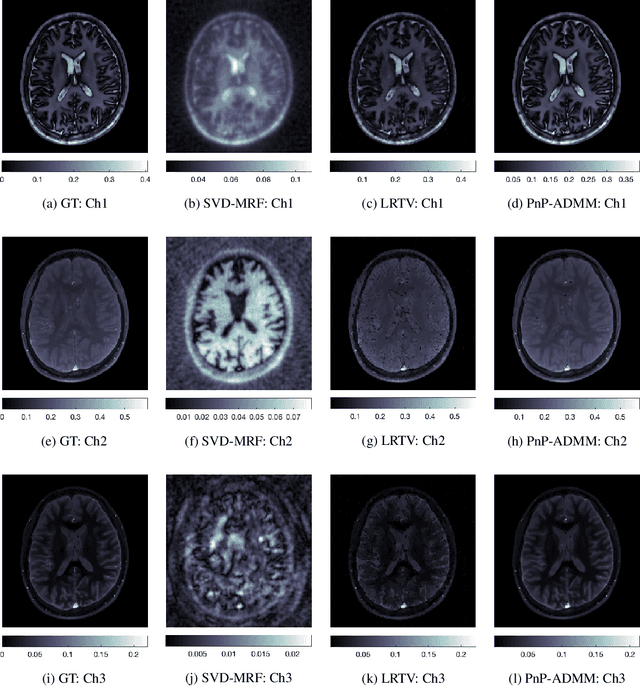

Abstract:Current spatiotemporal deep learning approaches to Magnetic Resonance Fingerprinting (MRF) build artefact-removal models customised to a particular k-space subsampling pattern which is used for fast (compressed) acquisition. This may not be useful when the acquisition process is unknown during training of the deep learning model and/or changes during testing time. This paper proposes an iterative deep learning plug-and-play reconstruction approach to MRF which is adaptive to the forward acquisition process. Spatiotemporal image priors are learned by an image denoiser i.e. a Convolutional Neural Network (CNN), trained to remove generic white gaussian noise (not a particular subsampling artefact) from data. This CNN denoiser is then used as a data-driven shrinkage operator within the iterative reconstruction algorithm. This algorithm with the same denoiser model is then tested on two simulated acquisition processes with distinct subsampling patterns. The results show consistent de-aliasing performance against both acquisition schemes and accurate mapping of tissues' quantitative bio-properties. Software available: https://github.com/ketanfatania/QMRI-PnP-Recon-POC